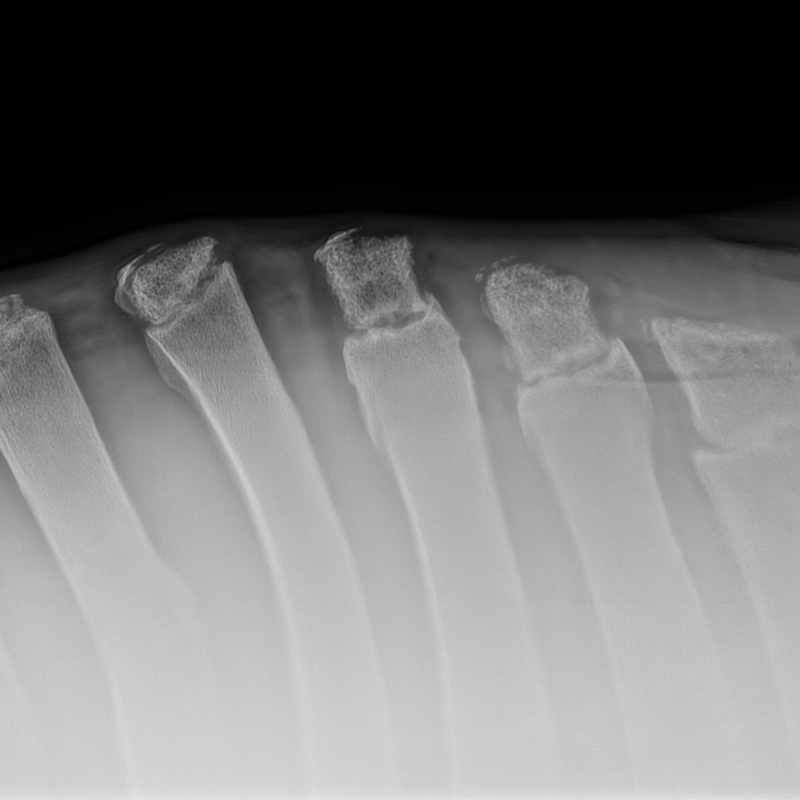

RADIOLOGIA DIGITALE AD ALTA DEFINIZIONE

Cuattro DR HD è l'ultimo sistema radiografico digitale ad alta definizione per piccoli animali ed equini prodotto dal fornitore leader di soluzioni radiografiche digitali veterinarie.

Innovativo, veloce, efficace, sicuro e ancora più brillante: l'ultimo sistema a raggi X, Cuattro DR HD soddisfa i più alti standard nella diagnostica radiografica veterinaria.

- Visualizza i dettagli come mai fino ad ora : 17x17'’ 100 microns High definition detectors combinati con la migliore tecnologia post-elaborazione nel nostro software per immagini di altissima qualità